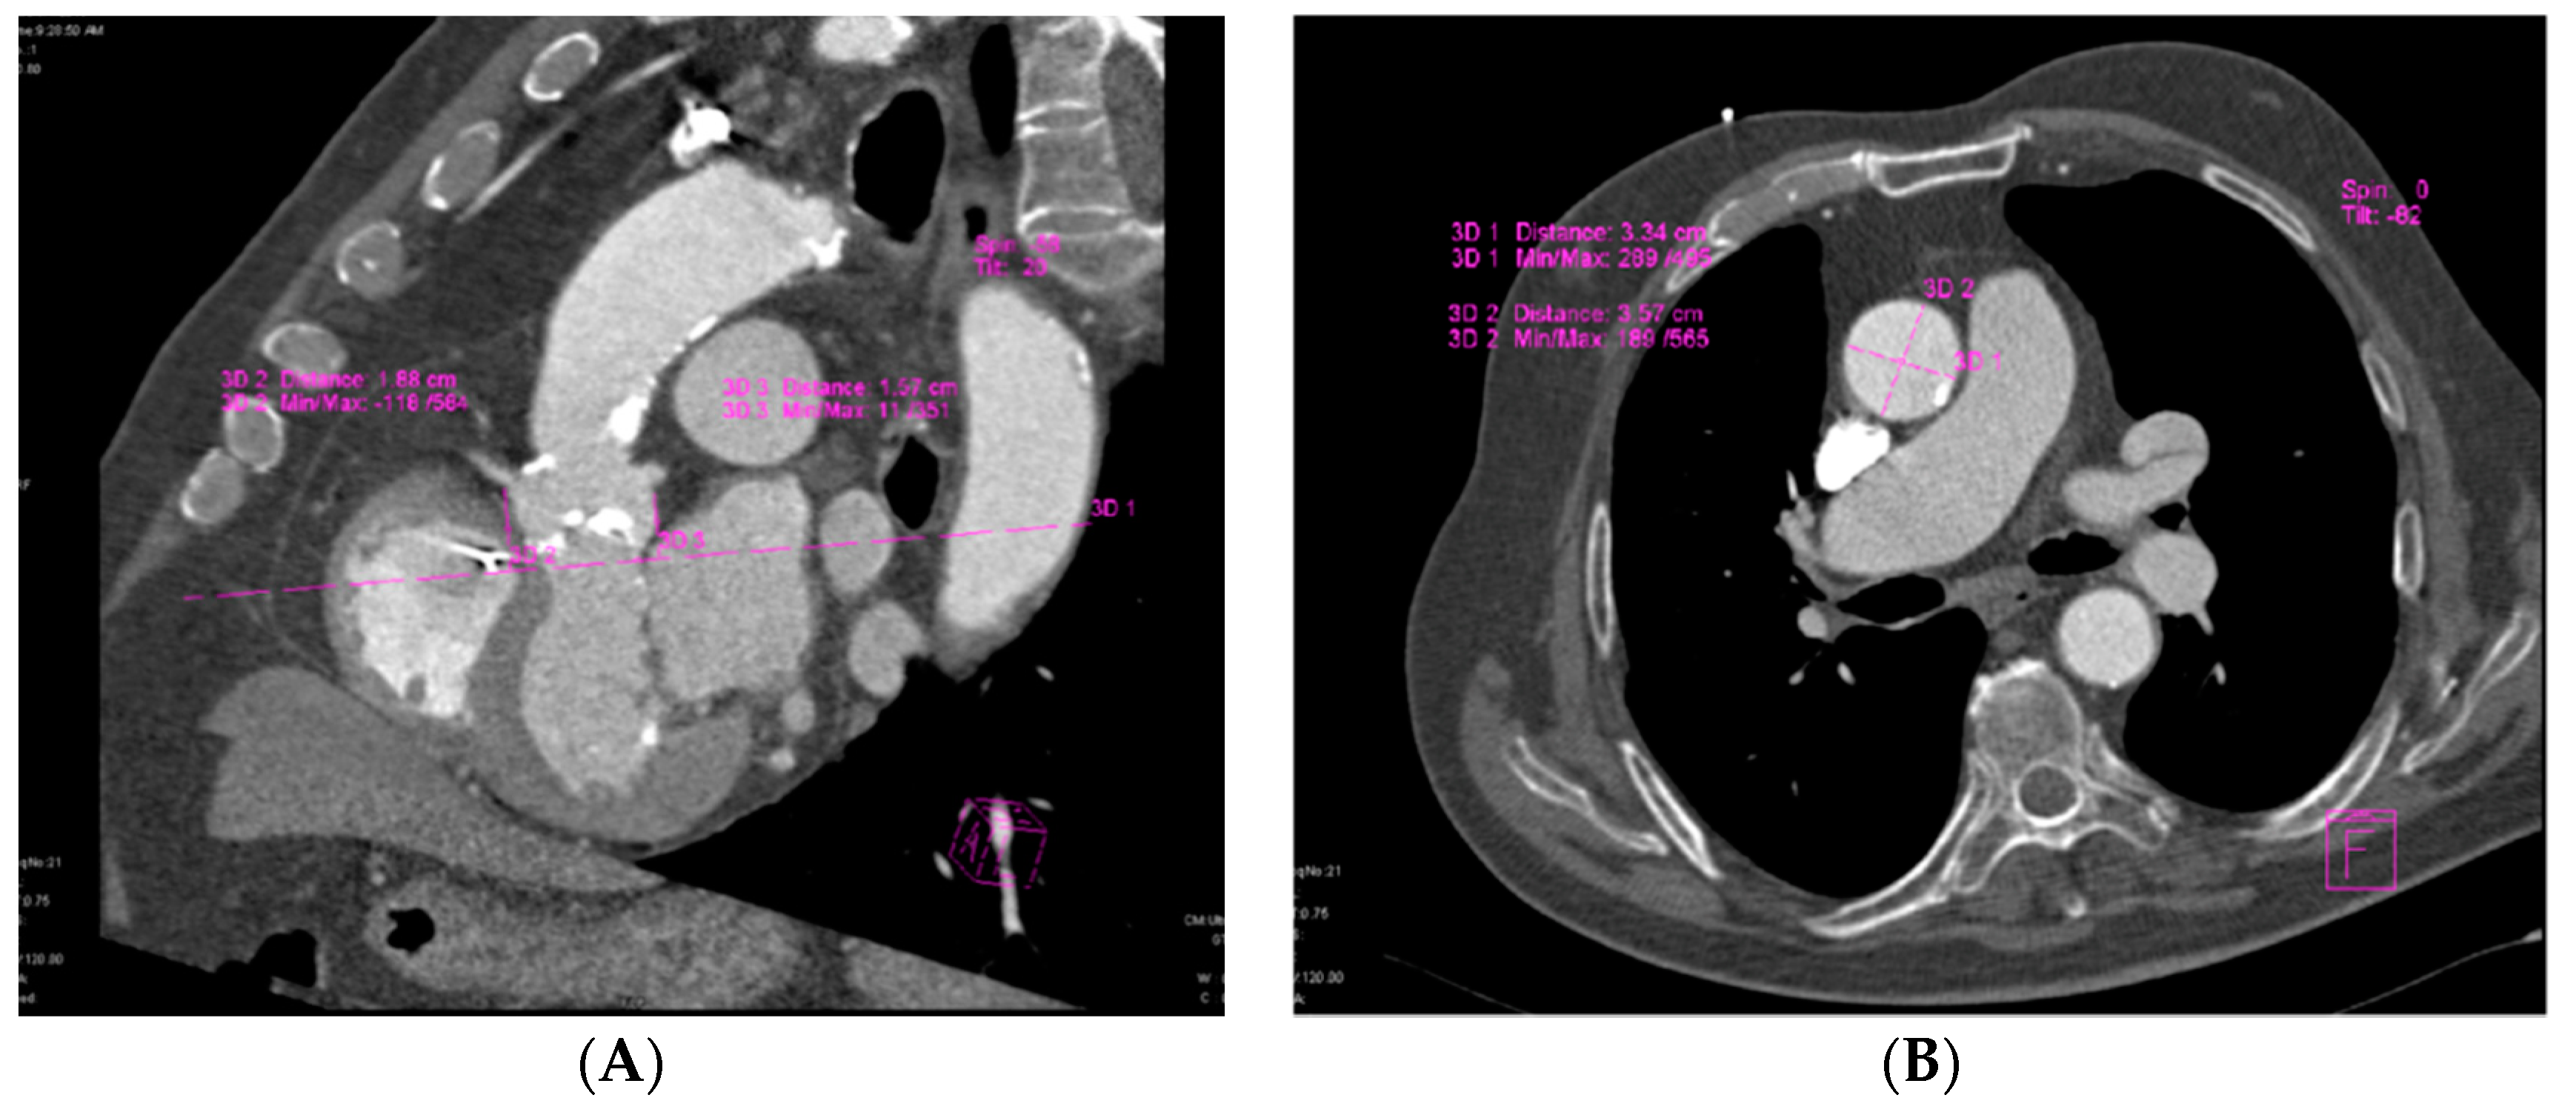

MDCT, which offers good visualization of aortic valve anatomy and extensive calcifications [7], provided accurate measurements for aortic annular sizing. The size of the implanted prosthesis correlated significantly with the MDCT aortic annular measurements (Figure 1).

Figure 1.

Assessment of aortic annular plane via MDCT: (A) Aortoventricular centerline; (B) Manual measurements of aortic annulus diameter.